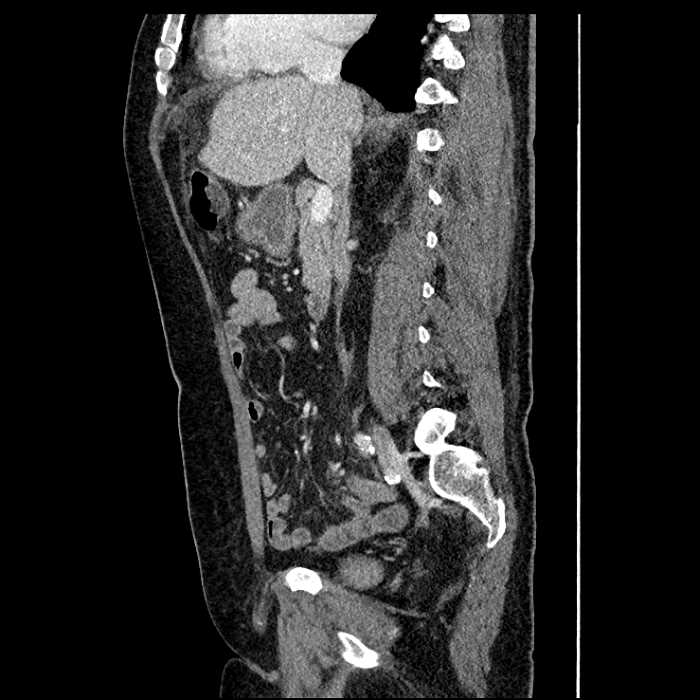

Age: 63

Sex: Male

Indication: Abdominal pain

• Mild mural thickening of a segment of the sigmoid colon with adjacent fat stranding and a 1.5 cm fluid and gas collection along the tip of an inflamed diverticulum

• Loss of the normal fat plane between this collection and adjacent loops of small bowel, which demonstrate mural thickening

• Hepatic abscess

Acute sigmoid diverticulitis complicated by a small contained perforation and a large abscess in the right hepatic lobe. Additional small subcapsular abscesses along the anterior margin of the left hepatic lobe.

Additionally, loss of the normal fat plane between the peridiverticular collection and adjacent thickened loops of small bowel raises the potential for an enterocolonic fistula.

Hepatic abscess showing the double target sign with low density internally surrounded by a thin inner enhancing rim (red arrow) and ill-defined outer low density rim (yellow arrow). Blue arrow indicates an internal septation. Red arrows: additional smaller subcapsular abscesses. Red arrow: focal contained perforation associated with diverticulitis.